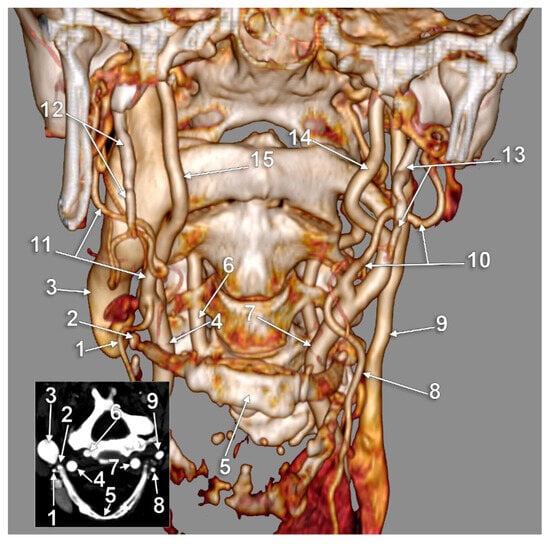

The Carotid–Hyoid Topography Is Variable

Manta, M.D.; Rusu, M.C.; Hostiuc, S.; Vrapciu, A.D.; Manta, B.A.; Jianu, A.M. The Carotid–Hyoid Topography Is Variable. Medicina 2023, 59, 1494. https://doi.org/10.3390/medicina59081494